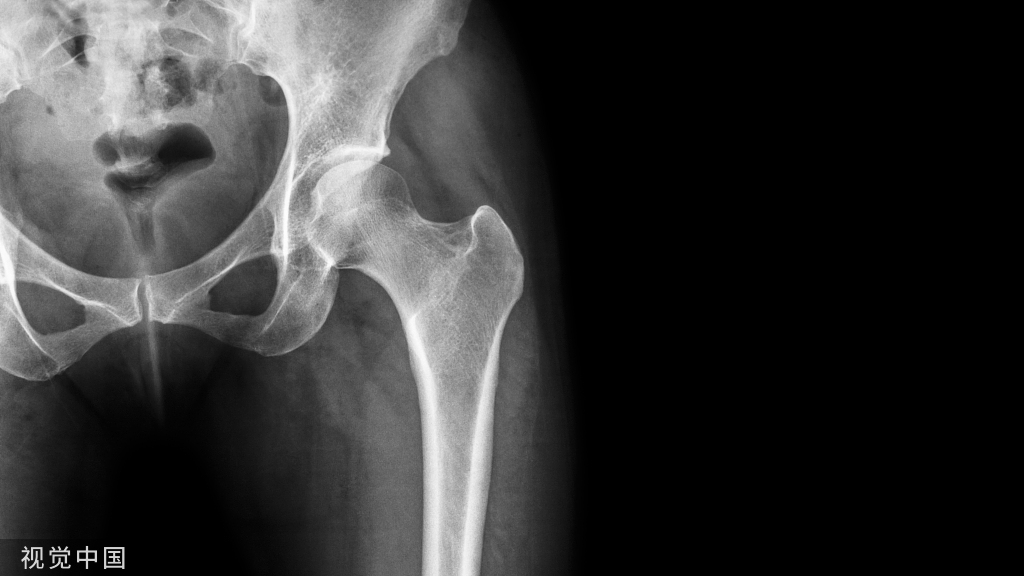

正常股骨头的软骨和软骨下骨结合致密,软骨下骨和其下的骨小梁自然延续,无明显界限:

尚未形成新月征的股骨头坏死